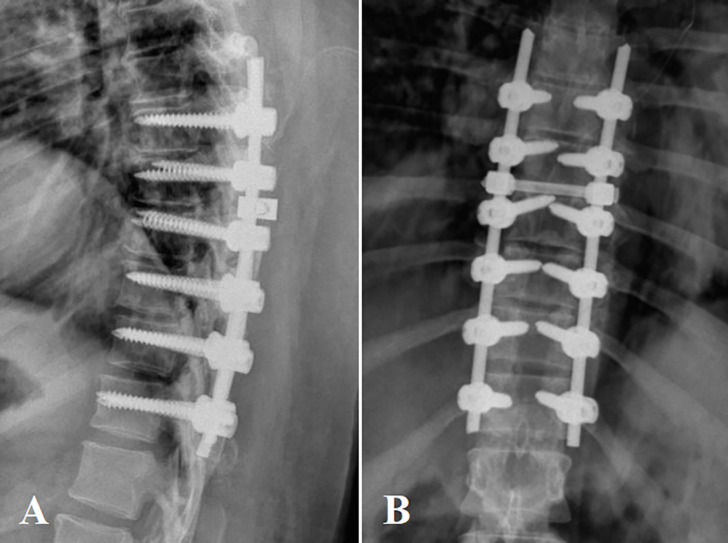

Thoracic ossification of the posterior longitudinal ligament (OPLL) is a rare condition that is mainly accompanied by cervical OPLL or ossification of thoracic ligamentum flavum. In case of causing neurological manifestations, it is preferred to treat the condition surgically. Several surgical procedures were introduced, including anterior, posterior, or combined approaches. Laminectomy with instrumented fusion is the most popular procedure utilized via the posterior approach. A 32-year-old obese woman, who suffered from back pain and weakness in both lower extremities for one month, was referred to our spine outpatient clinic. Imaging revealed lower thoracic OPLL (T7/T8 & T8/T9 & T9/T10). The posterior longitudinal ligament had a mixed ossification pattern (beaked and continuing cylindrical). To maintain thoracic spine stability and prevent future kyphosis, we performed laminectomy and long segment fixation (T7 to T12). The post-operative neurological examination revealed a considerable increase in muscle strength and significant pain relief.